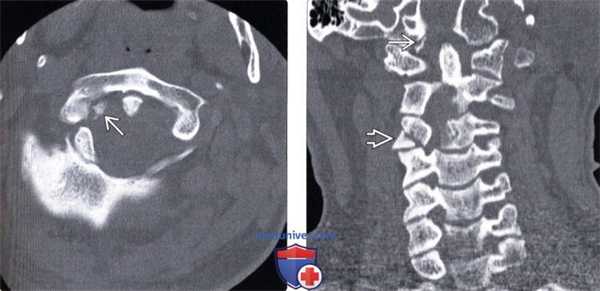

(Слева) КТ, аксиальный срез: отрыв правого мыщелка затылочной кости, фрагмент которого ротирован и смещен вниз и медиально, располагаясь над зубовидным отростком.

(Справа) На фронтальном КТ-срезе у этого же пациента определяется отрыв правого мыщелка затылочной кости, который смещен вниз и медиально и располагается над верхушкой зубовидного отростка.